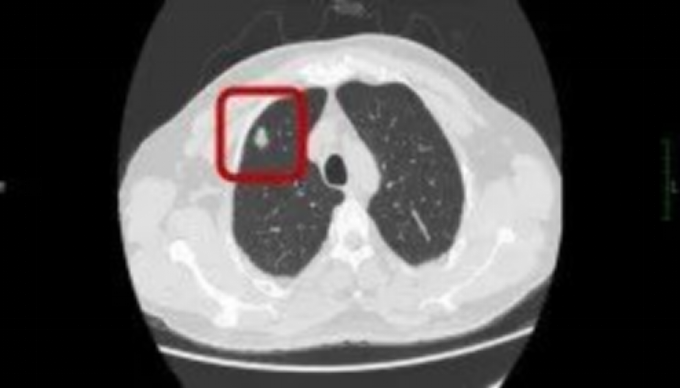

接诊后,肺小结节MDT门诊迅速启动多学科协作机制,由胸外科、医学影像科、呼吸与危重症医学科专家组成会诊团队。专家团队通过详细分析患者CT影像特征、病史及临床数据,一致判定该结节为高危结节,建议行微创手术治疗。朱先生充分信任团队,积极配合完成术前评估并顺利手术。术后病理结果证实为浸润性腺癌(cT1bN0M0),属早期肺癌,与专家团队术前诊断高度吻合。因发现及时、处置得当,患者术后无需辅助治疗,仅需定期随访即可。该病例的成功救治,印证了“早发现、早诊治”对肺结节管理的关键作用。